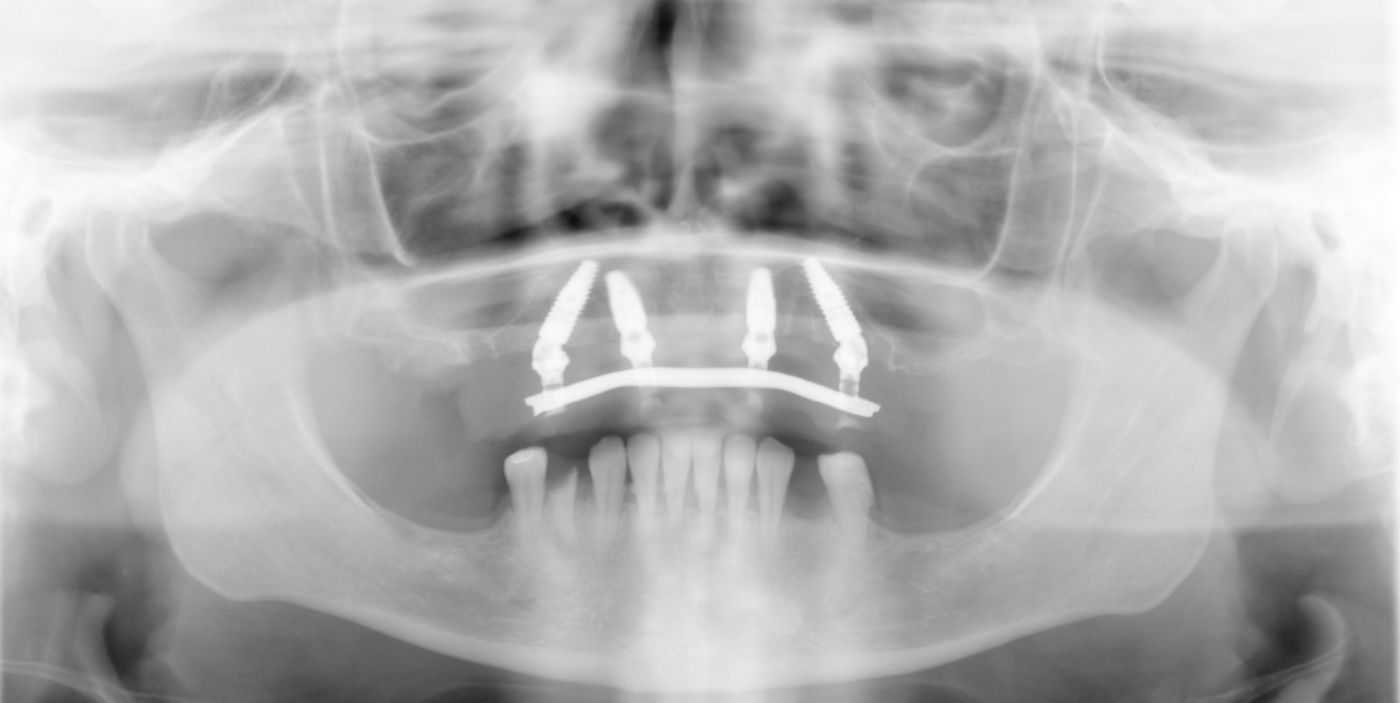

Ortopan snimka s privremenim All-on-4 radom